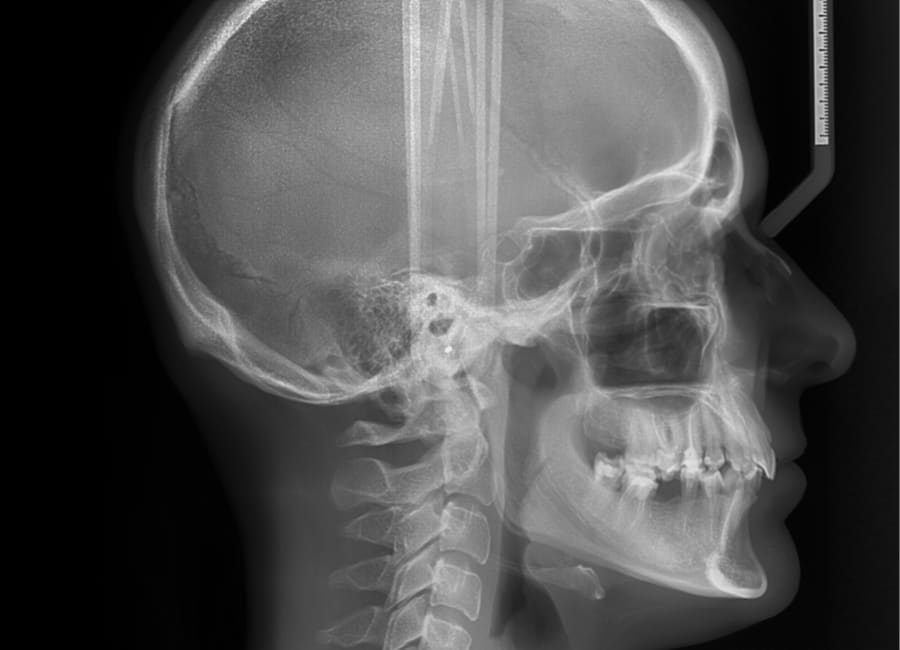

Cephalometric X-rays

A cephalometric X-ray is a specialized image that shows a side view of your head, including your teeth, jaw, and facial profile. This type of imaging helps your orthodontist understand how your teeth and jaw relate to each other and to your facial structure.

Cephalometric X-rays are frequently used to assess jaw growth, identify misalignments, and plan orthodontic treatments such as braces or aligners. They also help monitor changes over time, ensuring your treatment advances as planned and your bite stays in harmony with your facial proportions.